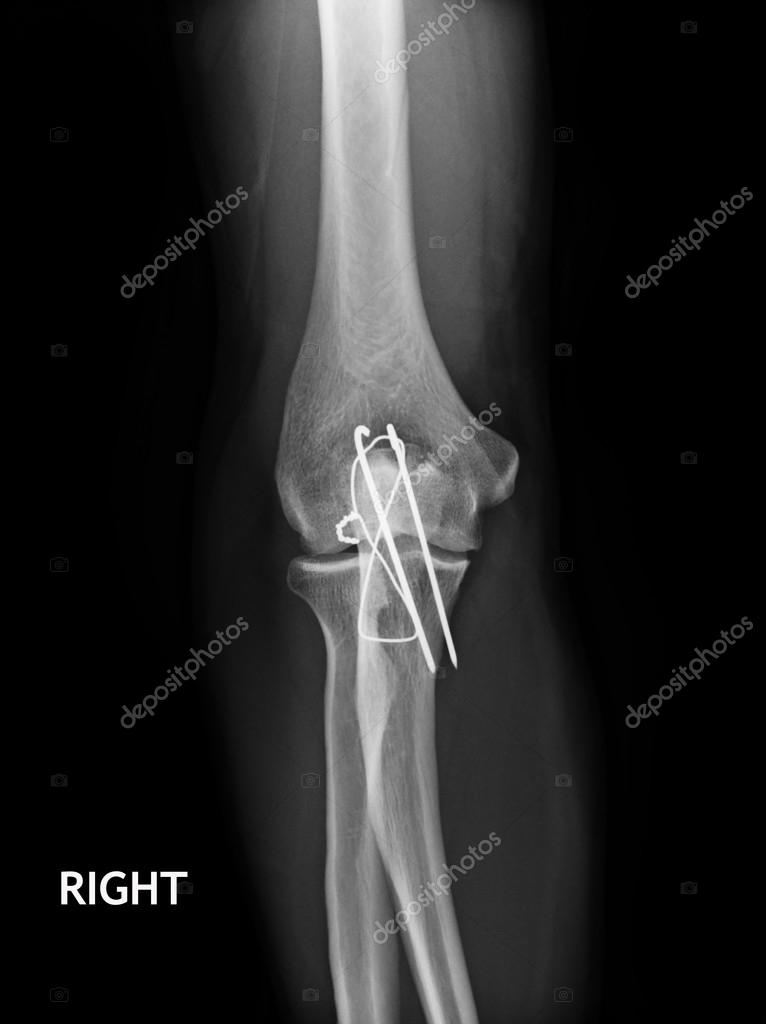

From depositphotos.com

Fracture Elbow, forearm xrays image showing plate and screw fixation Removing Plate And Screws From Elbow Screws removed to leave a hole in the bone, plates. Cover bone and tissue in packs. there are cases, though, when removing metal plates and screws, or other implants, may be necessary. orthopaedic hardware (plates, screws, nails and other pieces of metal or implants) can be removed. These are specially made from stainless steel or titanium for the.. Removing Plate And Screws From Elbow.